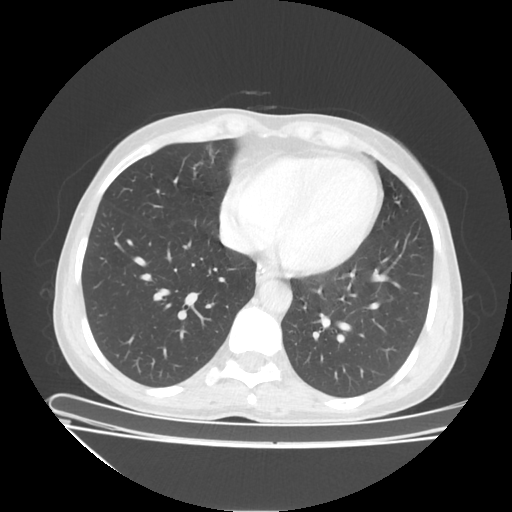

Original NATIVE CT scan (input)

Full window (WL 1023.5, WW 4095 β†’ Low βˆ’1024, High +3071)

Lung window (WL -600, WW 1500 β†’ Low βˆ’1350, High +150)

Mediastinum window (WL 40, WW 400 β†’ Low βˆ’160, High +240)